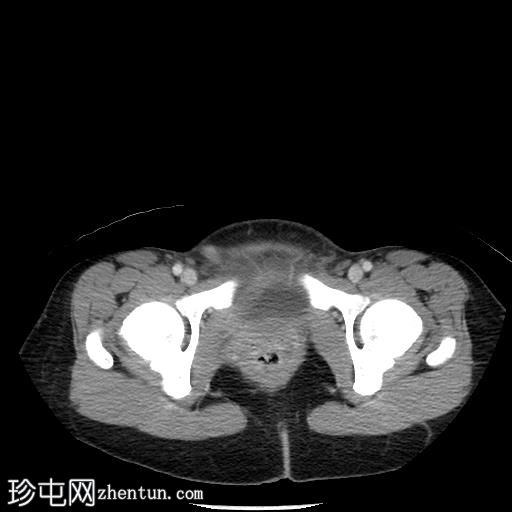

MRI

轴位T1加权像

脂肪抑制像

T1加权像平扫显示T1高信号,与CT上的高密度部分相对应,增强后无强化,符合血液成分表现。